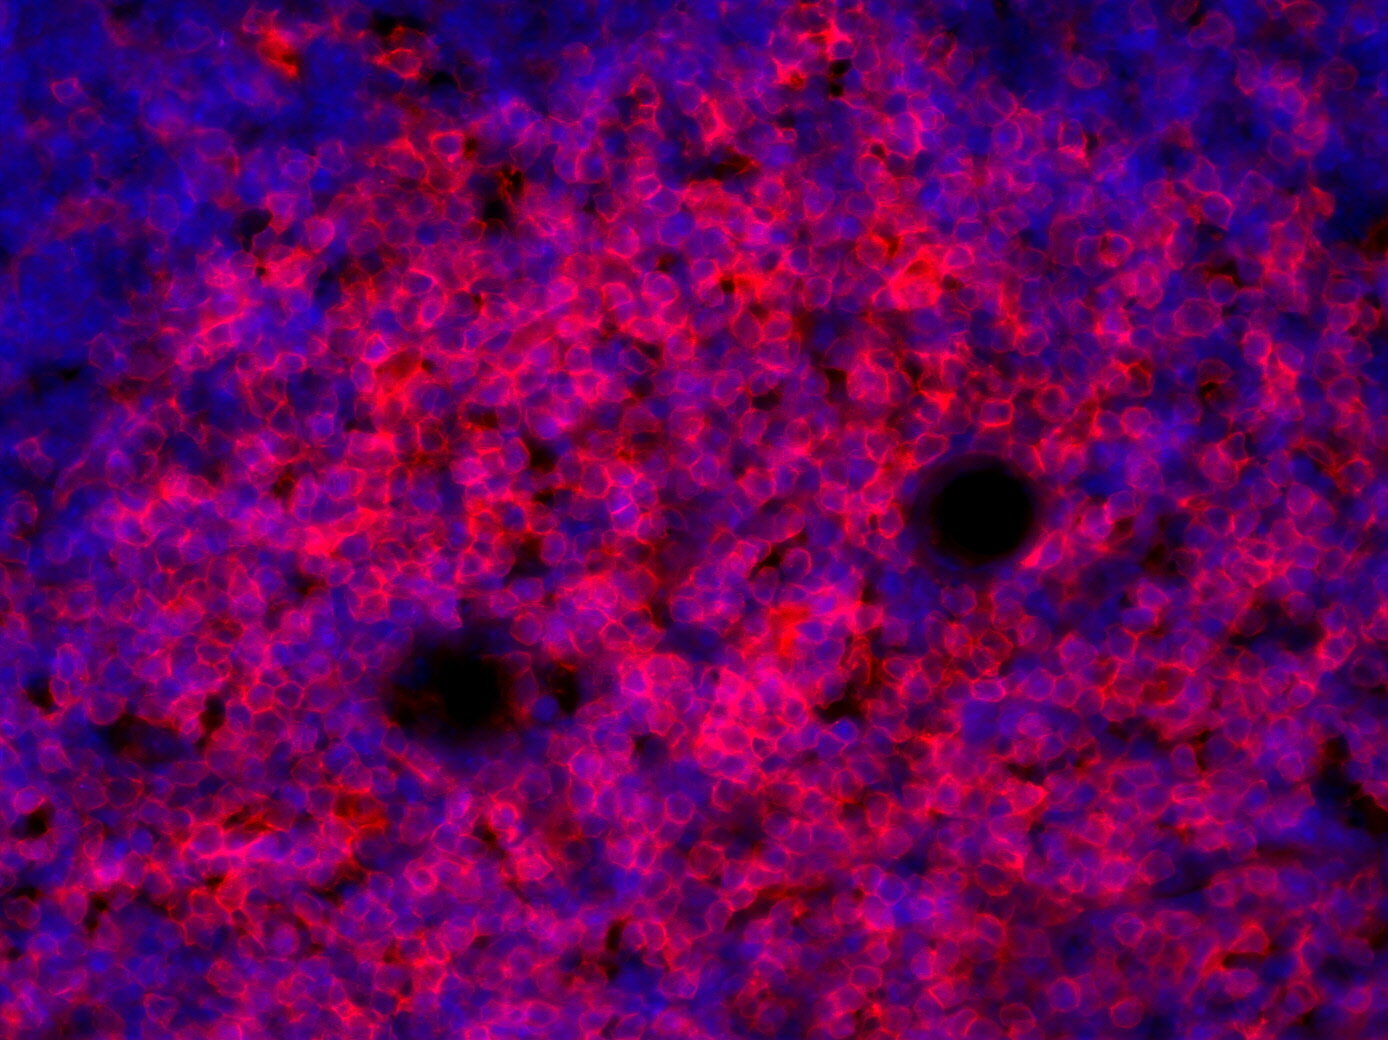

IHC-P: 1 : 900 gallery

Immunohistochemistry (IHC-P) of formalin fixed, paraffin embedded (FFPE) tissue (some antibodies require special antigen retrieval steps, please refer to the ”Remarks” section). Immunoreactivity is usually revealed by fluorescence or a chromogenic substrate.

EBioMedicine (2025) 112: 105543. HS-360 108 IHC-P; tested species: mouse

Frontiers in immunology (2022) 13: 875764. HS-360 108 IHC-P; tested species: mouse

Journal for immunotherapy of cancer (2021) 96: . HS-360 108 IHC-P; tested species: mouse